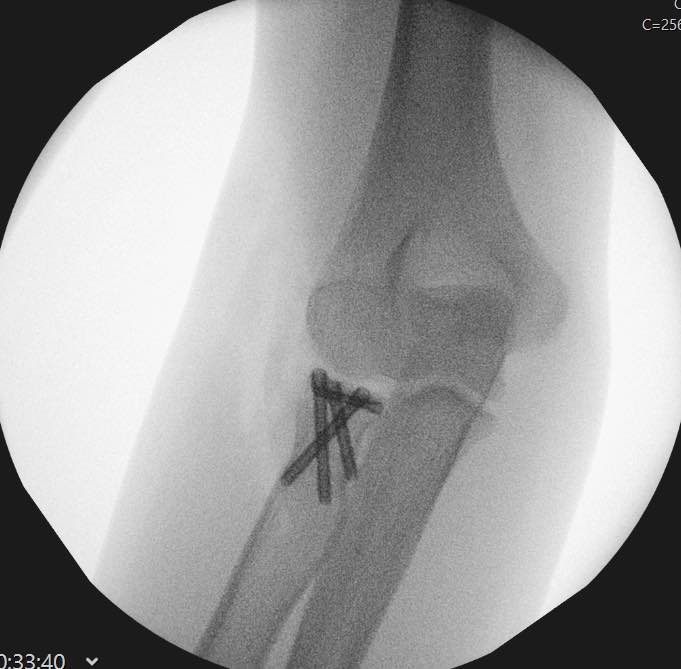

- Repair of torn ligaments (LUCL +/- MCL) with suture anchors

Most terrible triad injuries require surgical management to restore the functionality of your elbow. Surgery involves addressing all the injury components in your elbow. These may include fixation or replacement of the radial head, fixation or suturing of the coronoid and repair of the avulsed ligaments of your elbow.